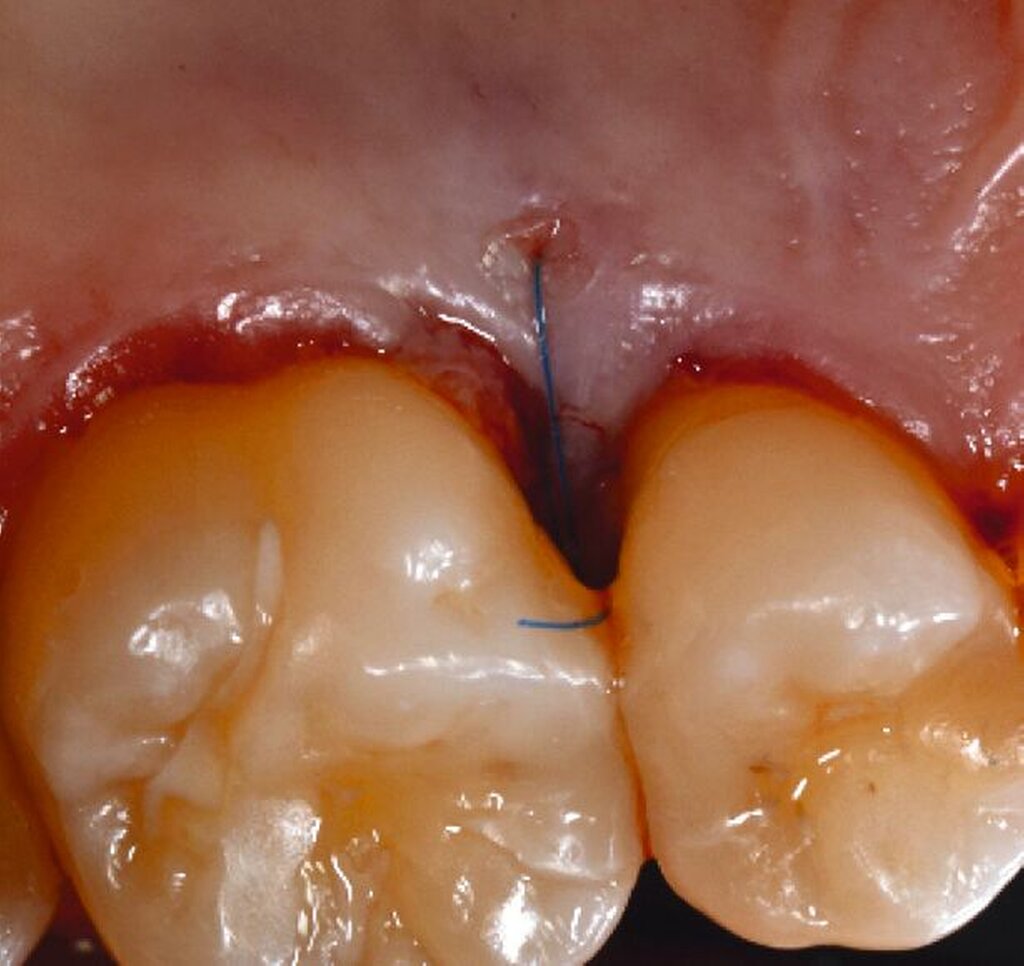

Alternativ kann eine GTR-Barrieremembran mit oder ohne zusätzlichen Defektfüller appliziert werden. Die Barrieremembran wird mit einer resorbierbaren Umschlingungsnaht befestigt, um den Furkationseingang abzudecken und die Wund- und Koagulumstabilisierung zu fördern. Um eine vollständige Abdeckung der Barriere zu ermöglichen, kann das Periost durchtrennt werden, um den Lappen leicht koronal zu verschieben. Der Lappen wird mit einer Umschlingungsnaht und Einzelknopfnähten über den vertikalen Entlastungsinzisionen oder mit interdentalen Nähten im Fall eines lateral extendierten Lappens in einer koronalen Position gesichert. Der Patient wird angewiesen, für einen Zeitraum von bis zu vier Wochen auf die mechanische Plaqueentfernung im Operationsgebiet zu verzichten. Während dieser Zeit werden Chlorhexidin-Spülungen oder -Gel verwendet. Der Patient kehrt zur Kontrolle der Wundheilung nach ein und zwei Wochen zurück, wenn die Nähte entfernt werden. Die Interdentalhygiene und die mechanische Plaqueentfernung werden nach vier Wochen wieder aufgenommen. Zudem wird ein individuelles Recallprogramm zur unterstützenden Parodontitistherapie (UPT) festgelegt.

Fall 1 – einfach

Fall 2 – fortgeschritten

Fall 3 – komplex